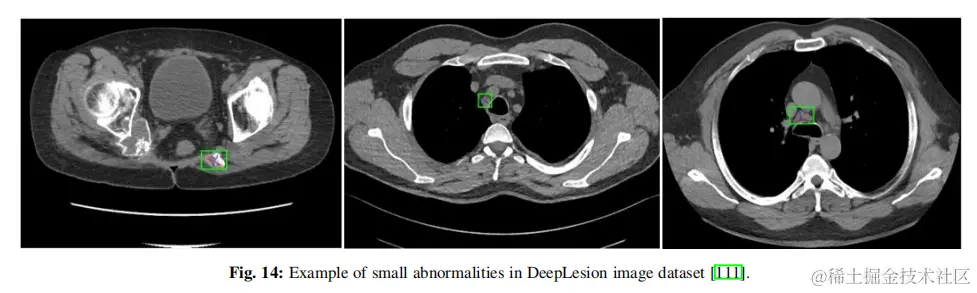

4.2.3醫學圖像中的小目標檢測 在醫學成像領域,專家的任務往往是早期發現和識別異常。即使是幾乎看不見或很小的異常細胞缺失,也會對患者造成嚴重的影響,包括癌症和危及生命的疾病。這些小目標可見於糖尿病患者視網膜異常、早期腫瘤、血管斑塊等。儘管這一研究領域具有關鍵的性質和潛在的危及生命的影響,但只有少數研究解決了在這一關鍵應用中與檢測小目標相關的挑戰。對於那些對這個主題感興趣的人,因為特定數據集的結果的可用性,論文選擇了深度病變CT圖像數據集作為基準。來自這個數據集的樣本圖像如圖14所示。該數據集被分為三組:訓練(70%)、驗證(15%)和測試(15%)集。表5比較了三種基於transformer的研究與兩級和一級檢測器的準確性和mAP(結果彙編自他們的論文)。MStransformer成為這個數據集上最好的技術,儘管競爭有限。它的主要創新在於自我監督學習和在一個分層transformer模型中加入一個掩碼機制。總的來説,該數據集的準確率為90.3%,mAP為89.6%,與其他醫學成像任務相比似乎沒有挑戰性,特別是考慮到一些腫瘤檢測任務幾乎是看不見的。